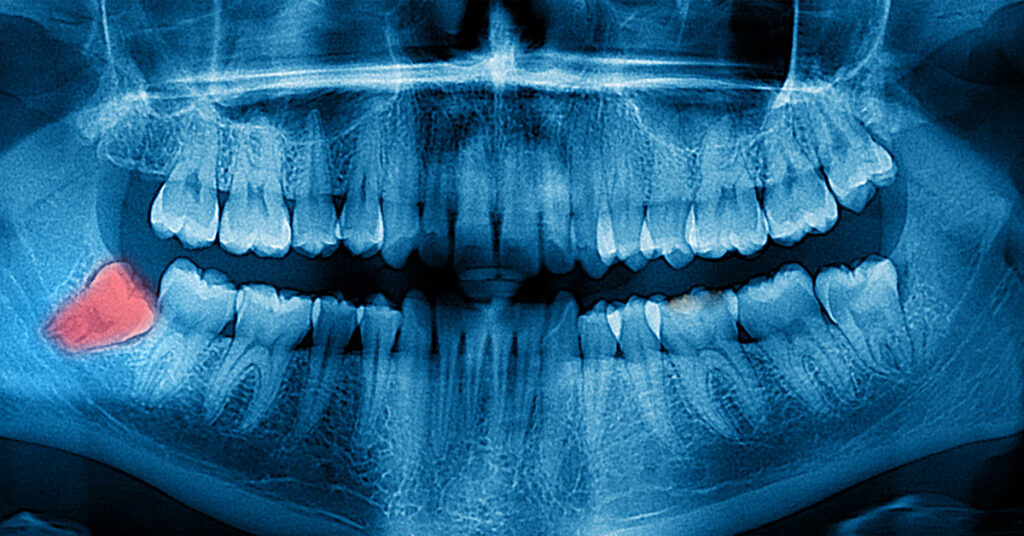

Descripción general. La extracción de muelas del juicio es un procedimiento quirúrgico para extraer una o más muelas del juicio —las cuatro piezas dentales permanentes de los adultos ubicadas en los extremos posteriores de la boca, tanto arriba como abajo—. Si una muela del juicio no tiene suficiente espacio para crecer (muela de juicio.

Diagnóstico. El dentista o cirujano dental pueden observar las muelas y la boca para determinar si tienes muelas del juicio incluidas u otra afección que pueda causar tus síntomas. Por lo general, dichos exámenes comprenden lo siguiente: Preguntas sobre los síntomas dentales y la salud en general. Controles del estado de los dientes y las.